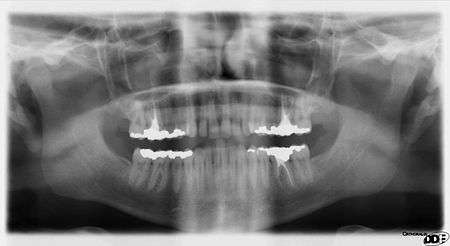

OPTs are used by health care professionals to provide information on:

- Impacted wisdom teeth diagnosis and treatment planning - the most common use is to determine the status of wisdom teeth and trauma to the jaws.

- Periodontal bone loss and periapical involvement.

- Finding the source of dental pain

- Assessment for the placement of dental implants

- Orthodontic assessment. pre and post operative

- Diagnosis of developmental anomalies such as cherubism, cleido cranial dysplasia

- Carcinoma in relation to the jaws

- Temporomandibular joint dysfunctions and ankylosis.

- Diagnosis of osteosarcoma, ameloblastoma, renal osteodystrophy affecting jaws and hypophosphatemia.

- Diagnosis, and pre- and post-surgical assessment of oral and maxillofacial trauma, e.g. dentoalveolar fractures and mandibular fractures.

- Salivary stones (Sialolithiasis).

- Other diagnostic and treatment applications.[1]